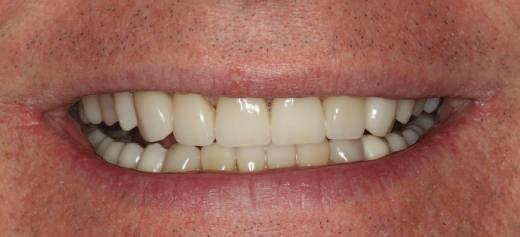

Atitudine: Până la dobândirea vindecării totale a ţesuturilor şi a implanturilor secundare s-au utilizat bonturi standard de titan. Fig. 18 prezintă bonturile individualizate maxilare şi mandibulare aplicate iar fig. 19 un prim-plan al cadranelor de partea dreaptă a pacientului, afişând finalizarea cazului la 15 luni după începerea tratamentului iniţial. Recesiile se pot obiectiva corespunzător 1.4. şi 1.3. În acest caz, s-a încercat minimizarea susceptibilităţii la recesie prin implicarea bonturilor temporare standard fixate cu şurub în cursul fazelor de vindecare pe toată durata etapelor iniţiale ale tratamentului.

În pofida acestor eforturi, totuşi, recesia a apărut în anumite regiuni unde implanturile erau plasate vestibular. Ulterior, s-a încercat grefarea ţesutui moale din jurul locaţiilor cu recesie, dar fără succes.

Rezultatul final al cazului 5 (fig. 19) prezintă recesie vestibulară de peste 2mm în jurul bonturilor cu sprijin implantar, fiind evidentă prezenţa unui ţesut moale foarte redus din cauza plasării vestibulare a implanturilor. Butler, Kinzer susţin premiza că trebuie să existe suficient volum osos vestibular, chiar şi atunci când implantul este plasat ideal, multe complicaţii fiind legate mai degrabă de poziţia implantului.

Cazul (5):

Bonturi conice utilizate ca bonturi temporare

Figurile

16, 17. Implanturile din prima etapă încărcate cu bonturi conice şi, în unele cazuri, omologii angulaţi.

18. Bonturile individualizate inserate.

19. Rezultat final la 15 luni după începerea tratamentului iniţial.

şi va induce resorbţie osoasă şi migraţia apicală a ţesutului (Saadoun & Touati). Dacă implantul nu este plasat mai palatinal şi la 3-4mm apical de marginea gingivală liberă pentru a asigura profilul de emergenţă adecvat, rezultatul estetic este compromis (Chu et al). Un studiu de 2 ani a demonstrat că implanturile poziţionate anterior au demonstrat o recesie uşor mai accentuată, decât implanturile posterioare (Bengazi et al). Plasarea vestibulară a implanturilor se poate vizualiza clar în cazul 5 (fig. 17) cu bonturile de vindecare în poziţie.